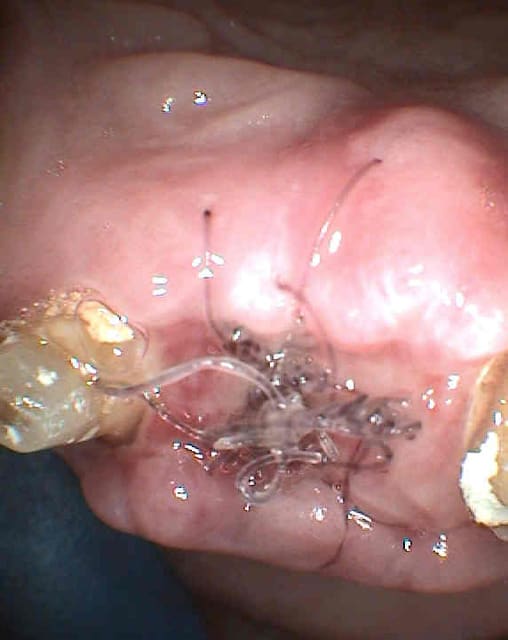

revu ce soir, je n'ai rien déposé, mais après un long examen et beaucoup d'interrogations, j'ai fait l'ouverture de la 13:

-compo volumineux

-douleur exacerbée au froid

-douleur a la palpation en regard de l'apex

-élargissement ligamentaire sur la radio.

pour la 12, il y a une douleur a la mmobilisation, mais radiologiquement, je ne vois rien.

je revois la patiente jeudi:

- si ca va mieux, c'est donc la 13

sinon, je ferais une dépose du tenon fibré sur 12, et examen au microscope opératoire du canal, pour detecter une éventuelle fracture ( la racine est rectiligne, je crois que je devrais y voir clair.

je vous laisse les clichés.

sur les photos, la gauche et la droite sont inversées